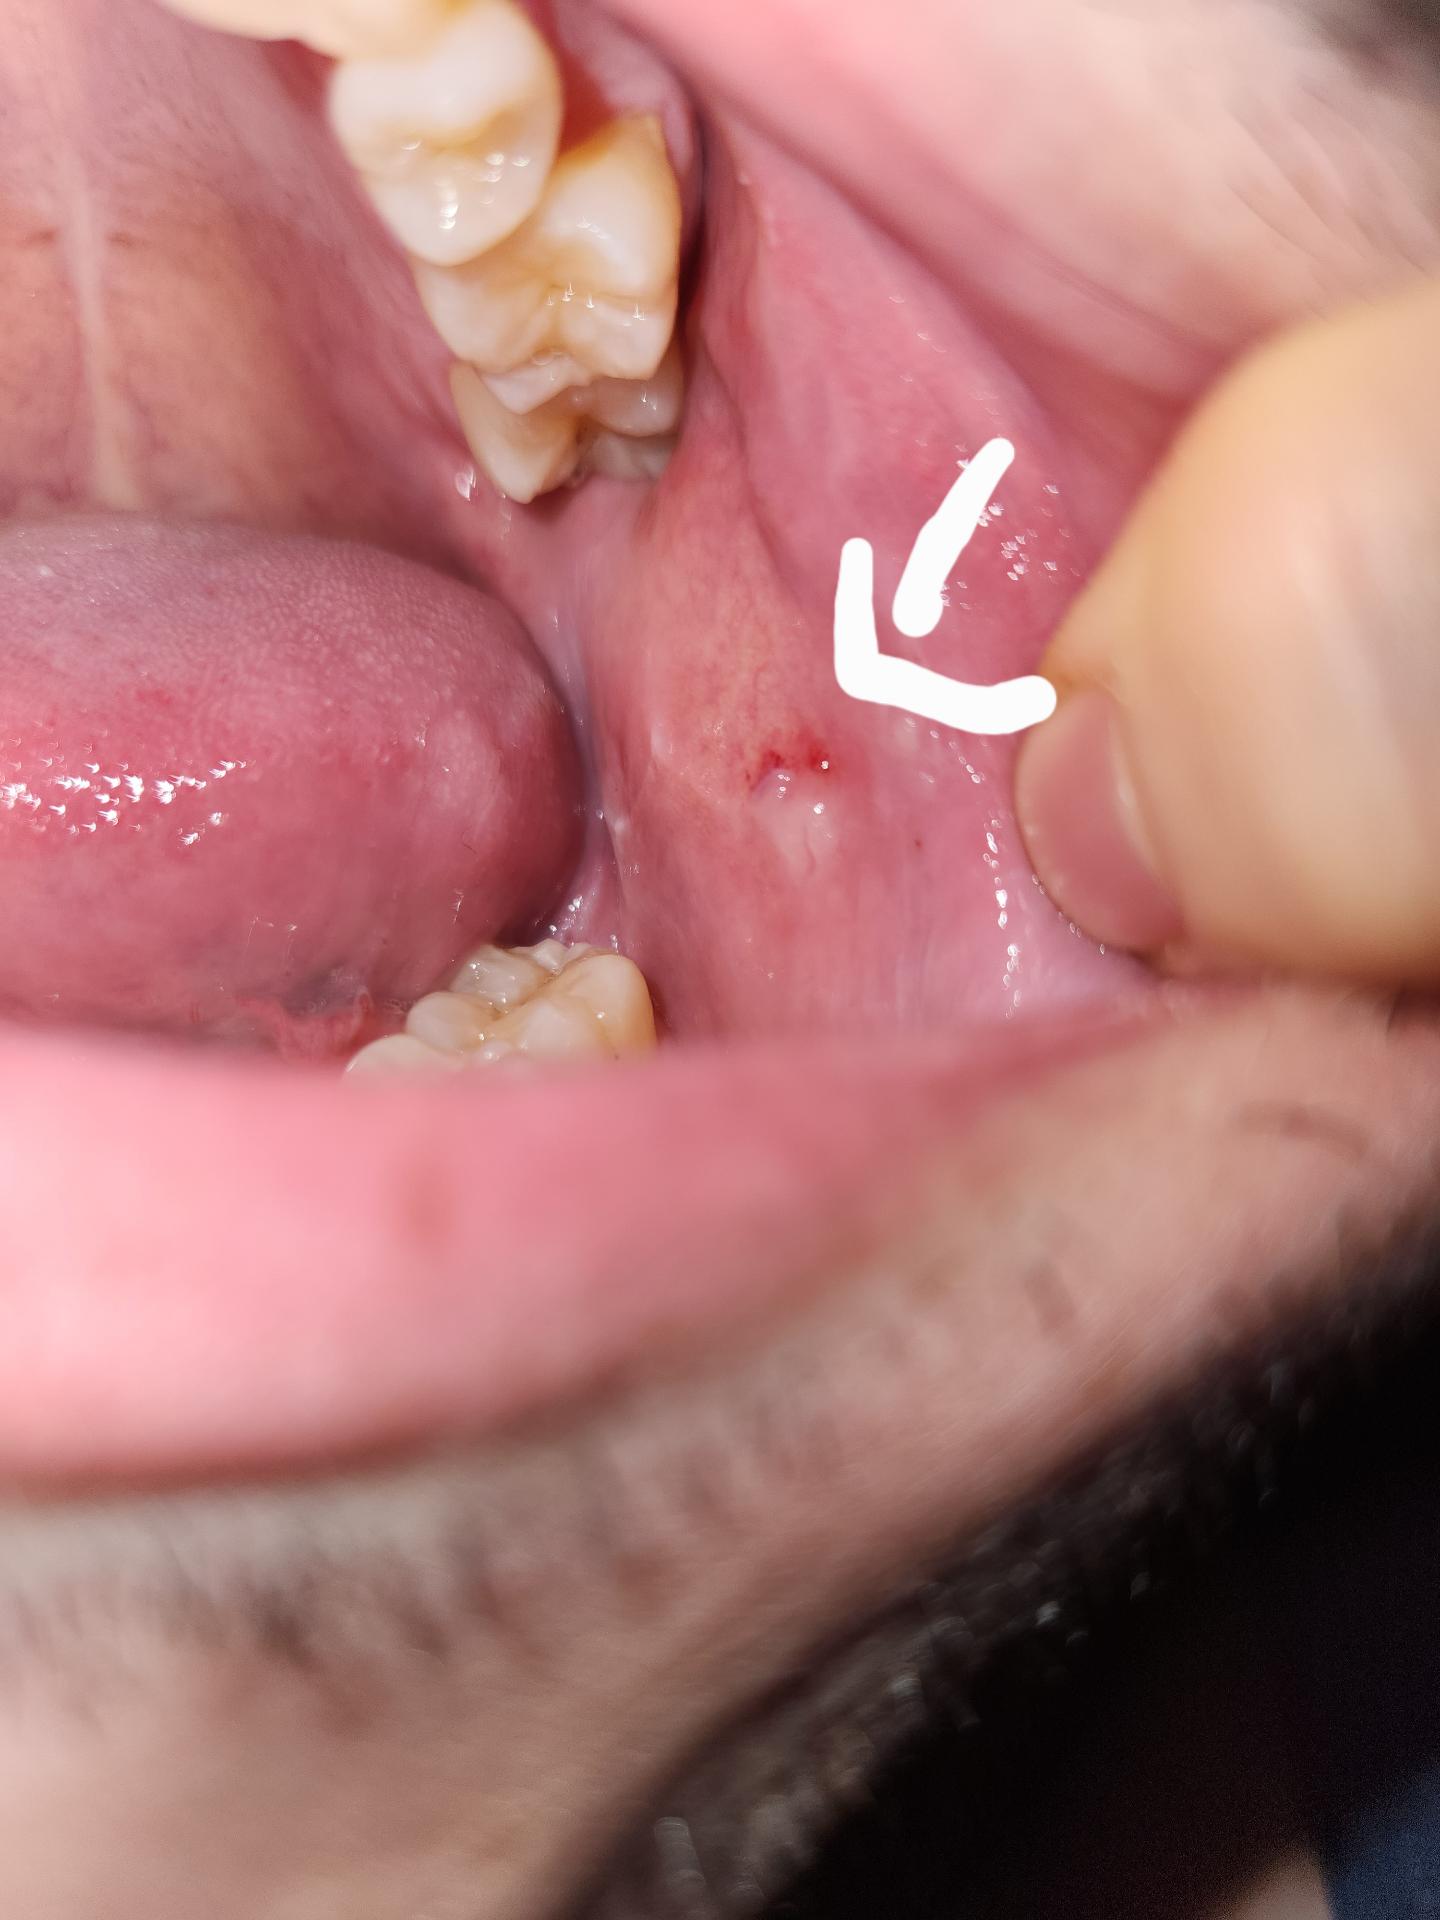

볼안쪽에 뭔가 있습니다 하얀색 멍울?

이게 머죠 하얀색 비슷무리한 좀 올라와 있습니다 피가 있는이유는 제가 터트릴러고 누른거라 생겼구요 피는 없습니다

하얀색 동그라미처럼 올라온 느낌이랄까

통증은없습니다 누르면평평해지거든여

침샘과 관련된 염증이거나 아니면 교합으로 인한 압흔같습니다 구강내과가서 정확히 진단받아보세요

볼살이 치아에 의해 씹히면서 자극을 받은 것으로 보이며 며칠 정도 조심해주셔야 겠습니다.

사진에 보이는건 볼살이 치아에 씹혀서 생긴 상처 입니다. 큰 문제가 잇는건 아니니 걱정하지마세요.